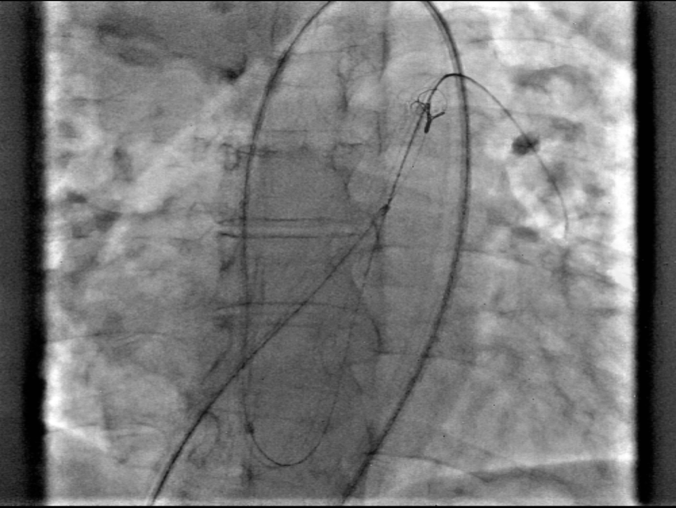

Ultrasound-guided dual access was completed, with a right femoral arterial as well as a venous approach. An aortogram was performed using the arterial approach, following introduction of a pigtail catheter at the level of the non-coronary aortic sinus, which showed a connection between the right atrium and the non-coronary aortic sinus (Figure 1, Video 1).

Figure 1. An aortogram revealing a communication between the right atrium and the non-coronary sinus of Valsalva (white arrow).